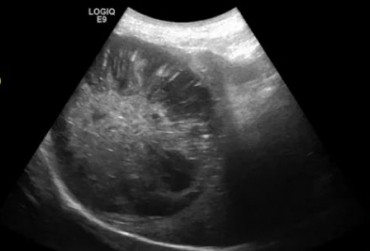

Określenie „rozpoznanie cioci Minnie” pochodzi ze Stanów Zjednoczonych i jest żartobliwym określeniem rozpoznania patognomonicznego, stosowanym głównie przez radiologów. Zwrot ten stał się popularny w latach 90. XX w. za sprawą strony internetowej o takim tytule. Obecnie to określenie stosuje się również w metodologii nauczania klinicznego. W artykule przedstawiono przypadki rozpoznań „cioci Minnie” z własnego archiwum ultrasonografii jamy brzusznej małych zwierząt.